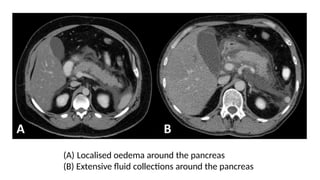

•Indications:

• Diagnostic uncertainty

• Severe pancreatitis – to distinguish interstitial from

necrotizing pancreatitis (Balthazar criteria)

• Organ failure, signs of sepsis or progressive clinical

deterioration

• Localised complication is suspected – fluid collection,

pseudocyst, pseudoaneurysm

(A) Localised oedema around the pancreas

(B) Extensive fluid collections around the pancreas

CT scan •Indications: • Diagnosticuncertainty • Severe pancreatitis – to distinguish interstitial from necrotizing pancreatitis (Balthazar criteria) • Organ failure, signs of sepsis or progressive clinical deterioration • Localised complication is suspected – fluid collection, pseudocyst, pseudoaneurysm

(A) Localised oedemaaround the pancreas (B) Extensive fluid collections around the pancreas